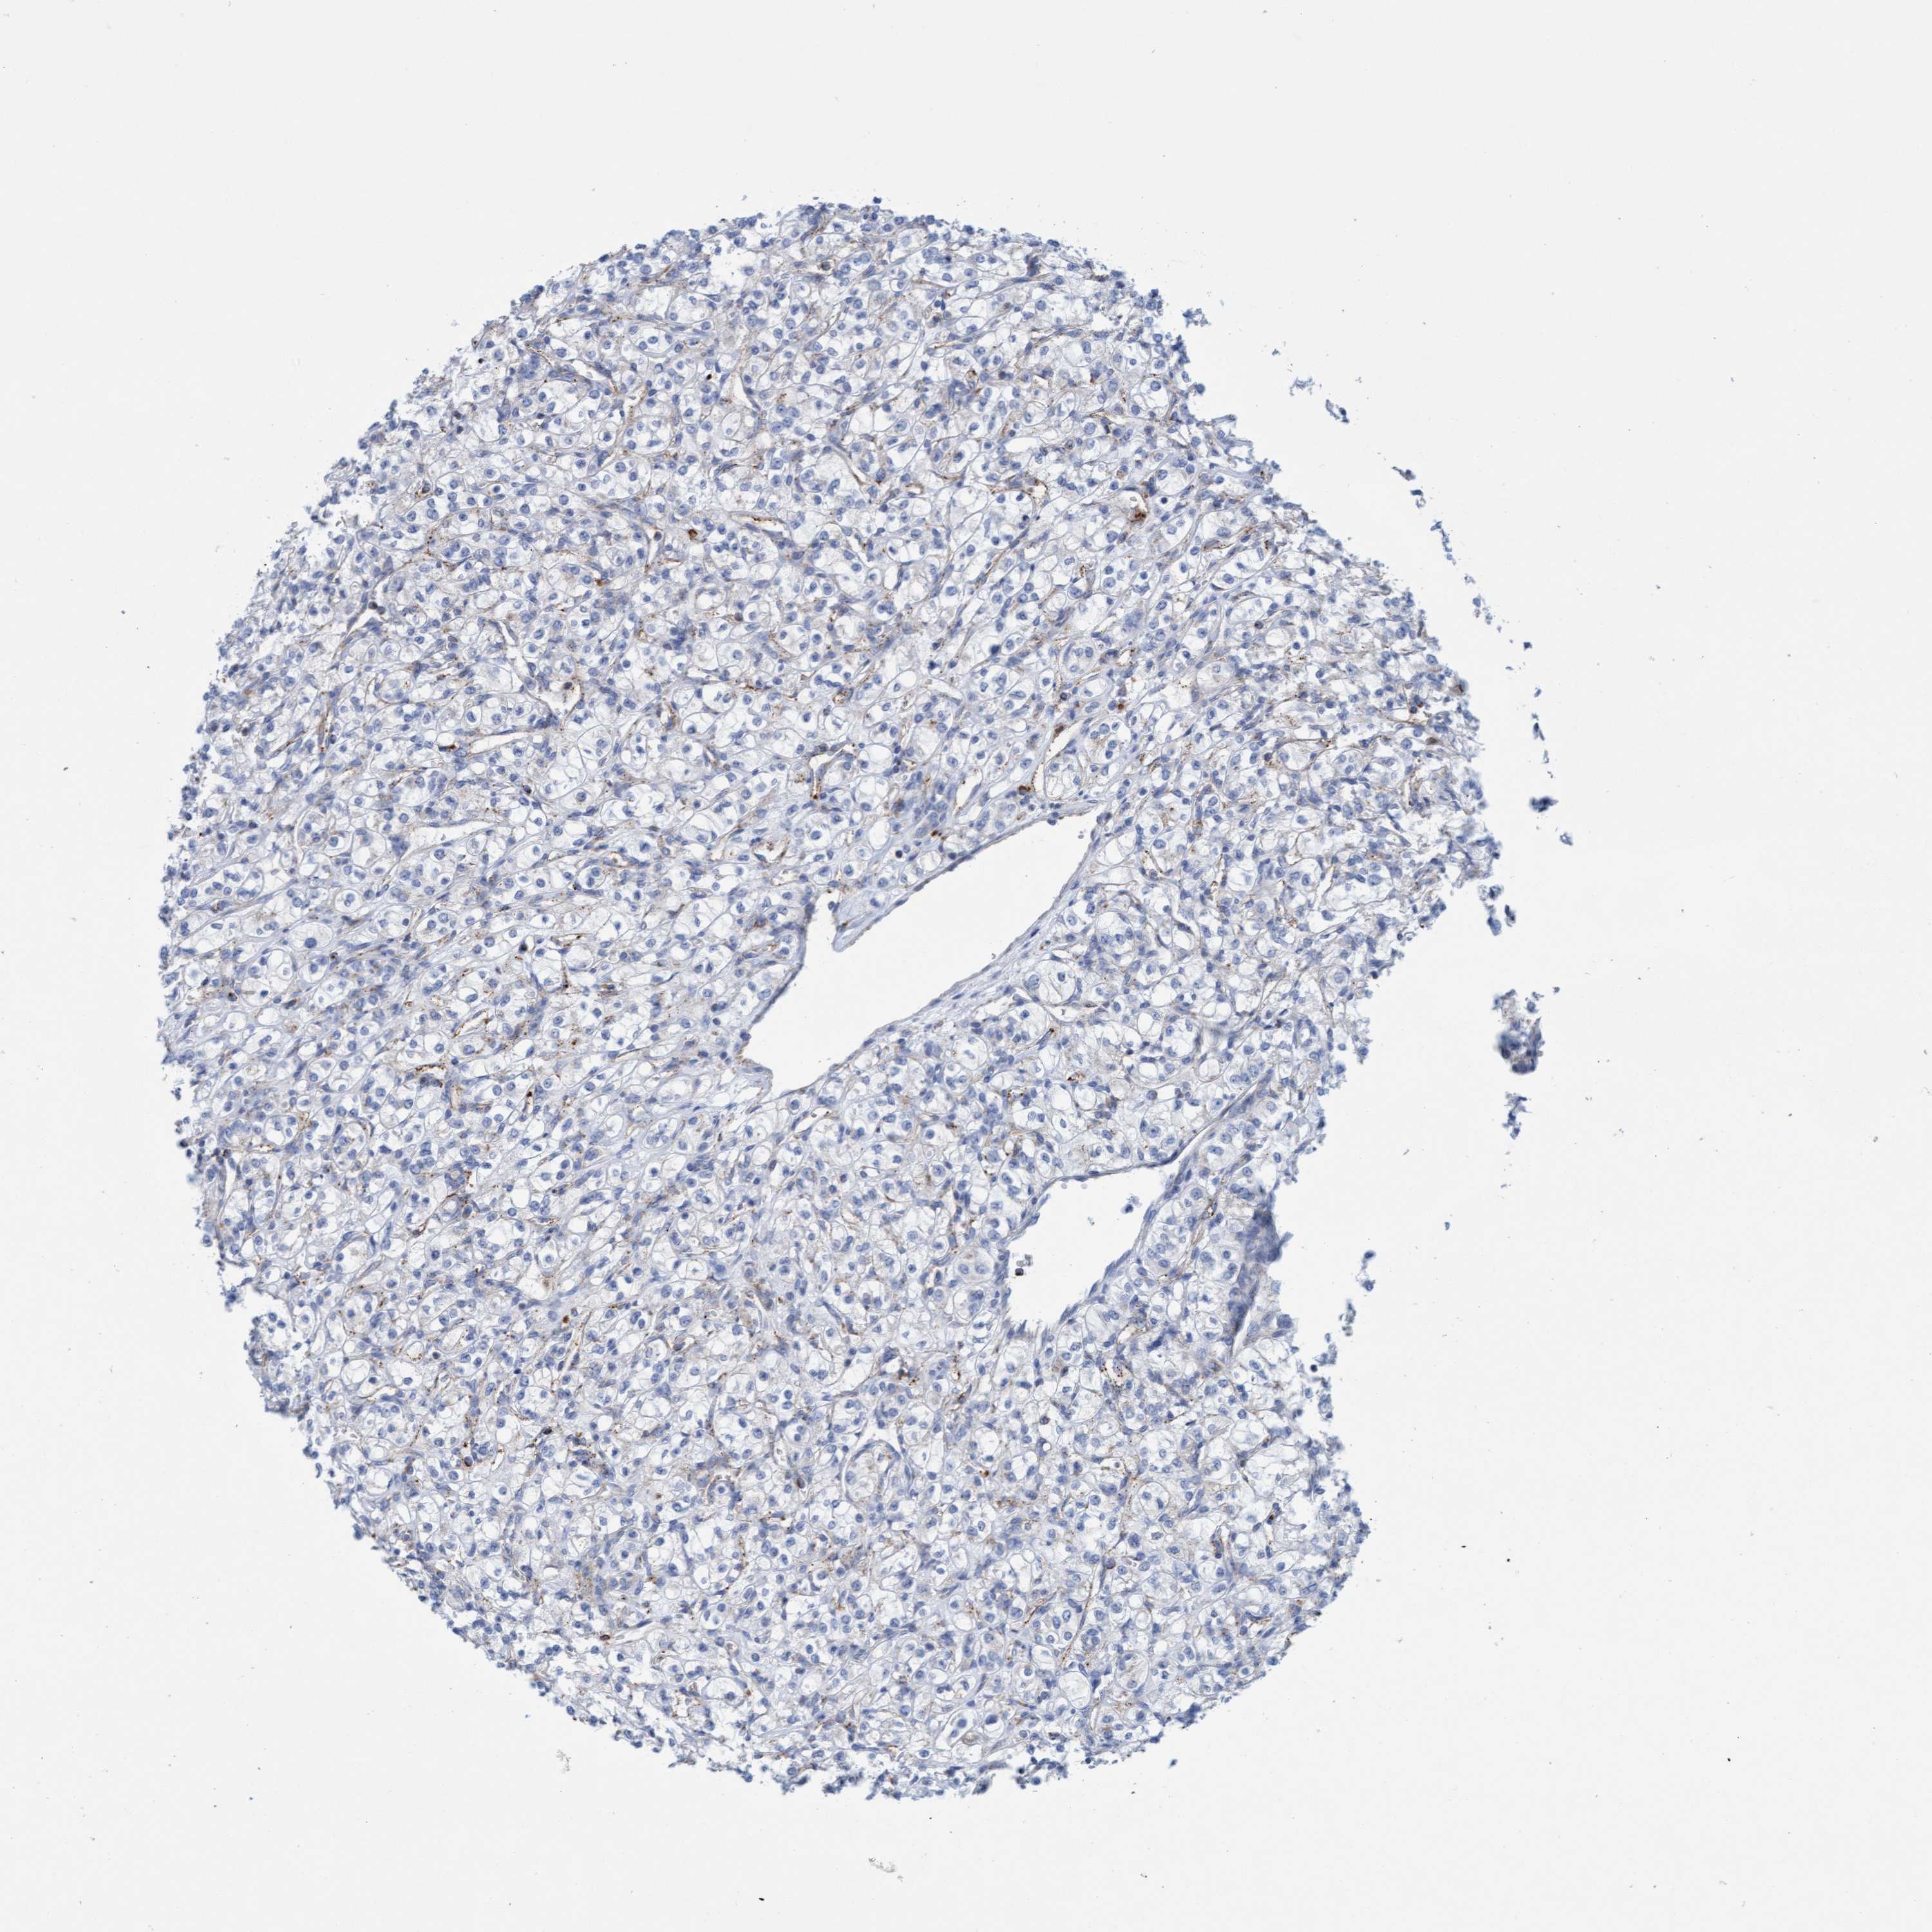

Average pTPM 16.1

Number of samples 100